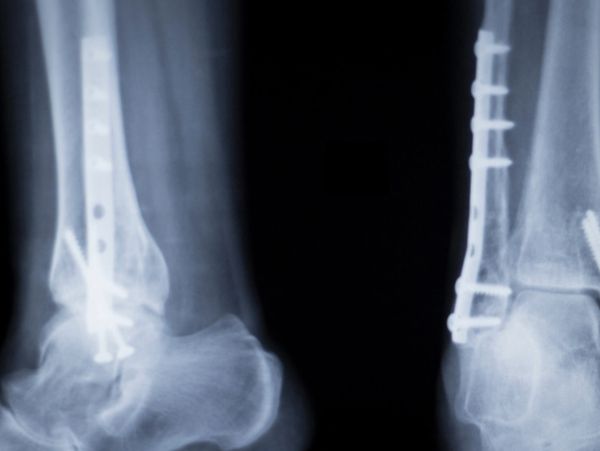

The Medical division provides engineering design and product development support for orthopedic and implantable medical devices intended to assist in bone stabilization and accelerate healing. Work within this sector emphasizes design precision, regulatory alignment, and compliance with FDA 510(k) premarket clearance pathways, supporting clients in bringing safe and effective solutions to market.

Experience includes the development of orthopedic constructs engineered to support skeletal stabilization and functional restoration across the human body. Designs incorporate advanced surface modeling techniques, analytical validation, and biocompatible material choices to achieve optimal performance, reliability, and manufacturability.